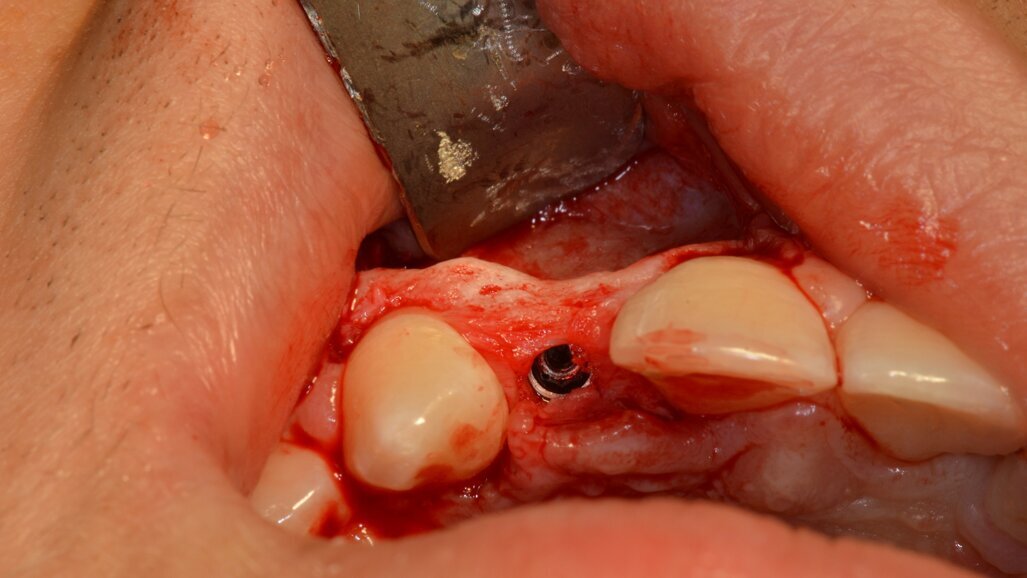

Amoxicillin (2 g) was given as antibiotic prophylaxis before the surgical intervention. A trapezoidal full-thickness flap was elevated from tooth #11 to tooth #13. After bone exposure, the implant site was prepared with a combined approach (piezoelectric and twist drill; Fig. 2). A tapered implant with a conical connection (3.6 × 12.0 mm; GTB, Advan) was inserted 1.5 mm below the crest in a palatal position (Figs. 3a & b). Afterwards, bone-promoting holes were made in the buccal bone and a cross-linked collagen membrane (Geistlich Bio-Gide, Geistlich Pharma) was secured with a single palatal pin and two buccal pins positioned between the roots of teeth #11 and 13. The gap was filled with deproteinised bovine bone mineral and autologous bone. After accurate periosteal releasing incisions, primary intention closure of the flaps was gained (Fig. 4). The patient was prescribed antibiotic and anti-inflammatory therapy (ibuprofen, every 8 hours; amoxicillin, every 12 hours), together with a 0.2% chlorhexidine mouthwash, and given instructions on postoperative care. Postoperative healing was uneventful, and the sutures were removed after 14 days.